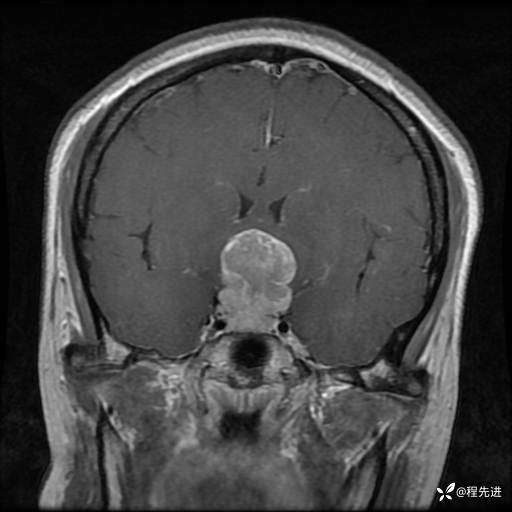

MRI平扫+增强:

T1:

T1+C: